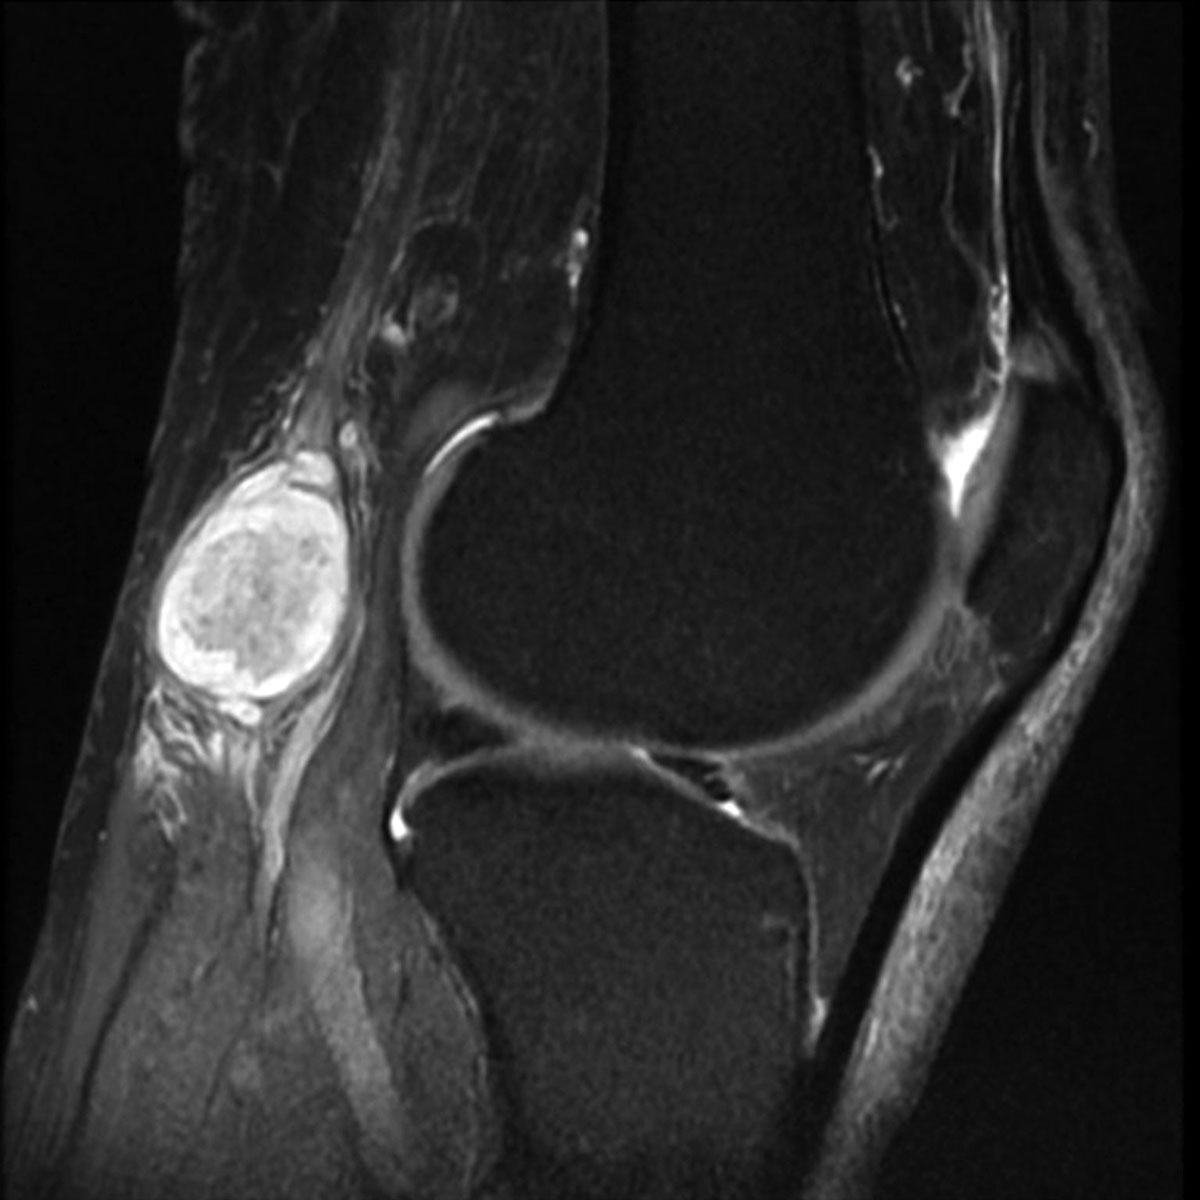

Диагностика данного заболевания начинается с опроса врача о симптомах и особенностях начала болезни. Затем специалист проводит пальпацию опухолевидного образования в задней подколенной ямке, чтобы оценить его консистенцию и наличие болезненности. Также важно проверить объем активных движений в коленном суставе. После сбора анамнеза и проведения объективного осмотра пациенту назначается ультразвуковое исследование. Этот метод позволяет визуализировать кисту, а также определить ее размеры и точное местоположение.

Врач, занимающийся ультразвуковой диагностикой, может установить стадию развития доброкачественного образования. Более точный диагноз устанавливается после проведения магнитно-резонансной томографии (МРТ). Этот современный метод лучевой диагностики помогает определить размеры, расположение, стадию развития и причины возникновения патологического процесса в тканях. Диафаноскопия является одним из самых простых и безопасных способов диагностики кисты Бейкера. С помощью этого метода врач может «просветить» доброкачественную опухоль в подколенной ямке.